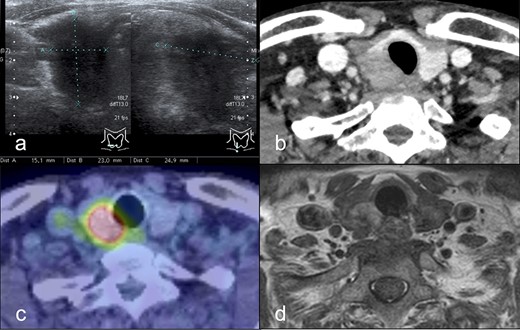

A 66-year-old man with hoarseness and coughing for more than a month was referred to our hospital for further investigation. He also had a palpable mass at the right thyroid lobe. Blood examinations showed no abnormalities in thyroid function (Table 1). Ultrasonography showed a hypoechoic nodule (15 × 23 × 25 mm) at the inferior pole of the right thyroid lobe (Fig. 1a) with bilateral enlarged cervical lymph nodes (10 mm). Contrast-enhanced computed tomography (CT) revealed the mass (18 × 24 × 26 mm) in equilibrium phase without contrast effect (Fig. 1b). The 2-deoxy-2-[18F] fluoro-D-glucose positron emission tomography showed high accumulation in the mass, whereas the cervical lymph nodes did not show accumulations (Fig. 1c). Magnetic resonance imaging showed the 30 mm diameter mass with mildly high signal on Dixon-T2-weighted imaging and suggested tracheal invasion and extraparenchymal extension (Fig. 1d). Flexible laryngeal fiberscopy showed right vocal cord paralysis. Ultrasound-guided fine-needle aspiration cytology indicated an atypical cell mass with a higher cell density and cumulation from the thyroid tumor, which was dominantly composed of small follicular structures without apparent papillary structures. However, the cells showed nuclear groove-like irregularities and intranuclear vacuoles, suggesting differentiated thyroid cancer.

(a) Cervical ultrasound examination: a hypoechoic nodule with indistinct borders and irregular margins (15 × 23 × 25 mm) was found at the inferior pole of the right lobe. (b) Dynamic CT scan: a mass lesion (18 × 24 × 26 mm) was found in the inferior pole of the right lobe thyroid gland without contrast effect in equilibrium phase. (c) PET/CT scan: FDG hyperaccumulation was observed in a nodule (~25 mm diameter) at the inferior pole of the right lobe of the thyroid gland. (d) MRI scan: A mass (30 mm diameter) with mildly high signal on Dixon-T2-weighted imaging was found at the inferior pole of the right lobe of the thyroid gland, and tracheal invasion. Extracapsular invasion was suspected. Abbreviations: CT, computed tomography; PET, positive emission tomography; FDG, fluorodeoxyglucose; MRI, magnetic resonance imaging.